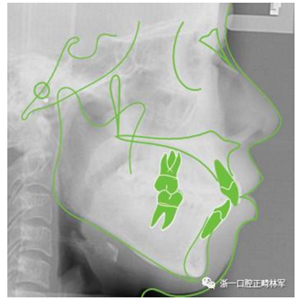

治療前側(cè)位片

頭影測(cè)量分析

Ricketts分析

Andrews六要素分析